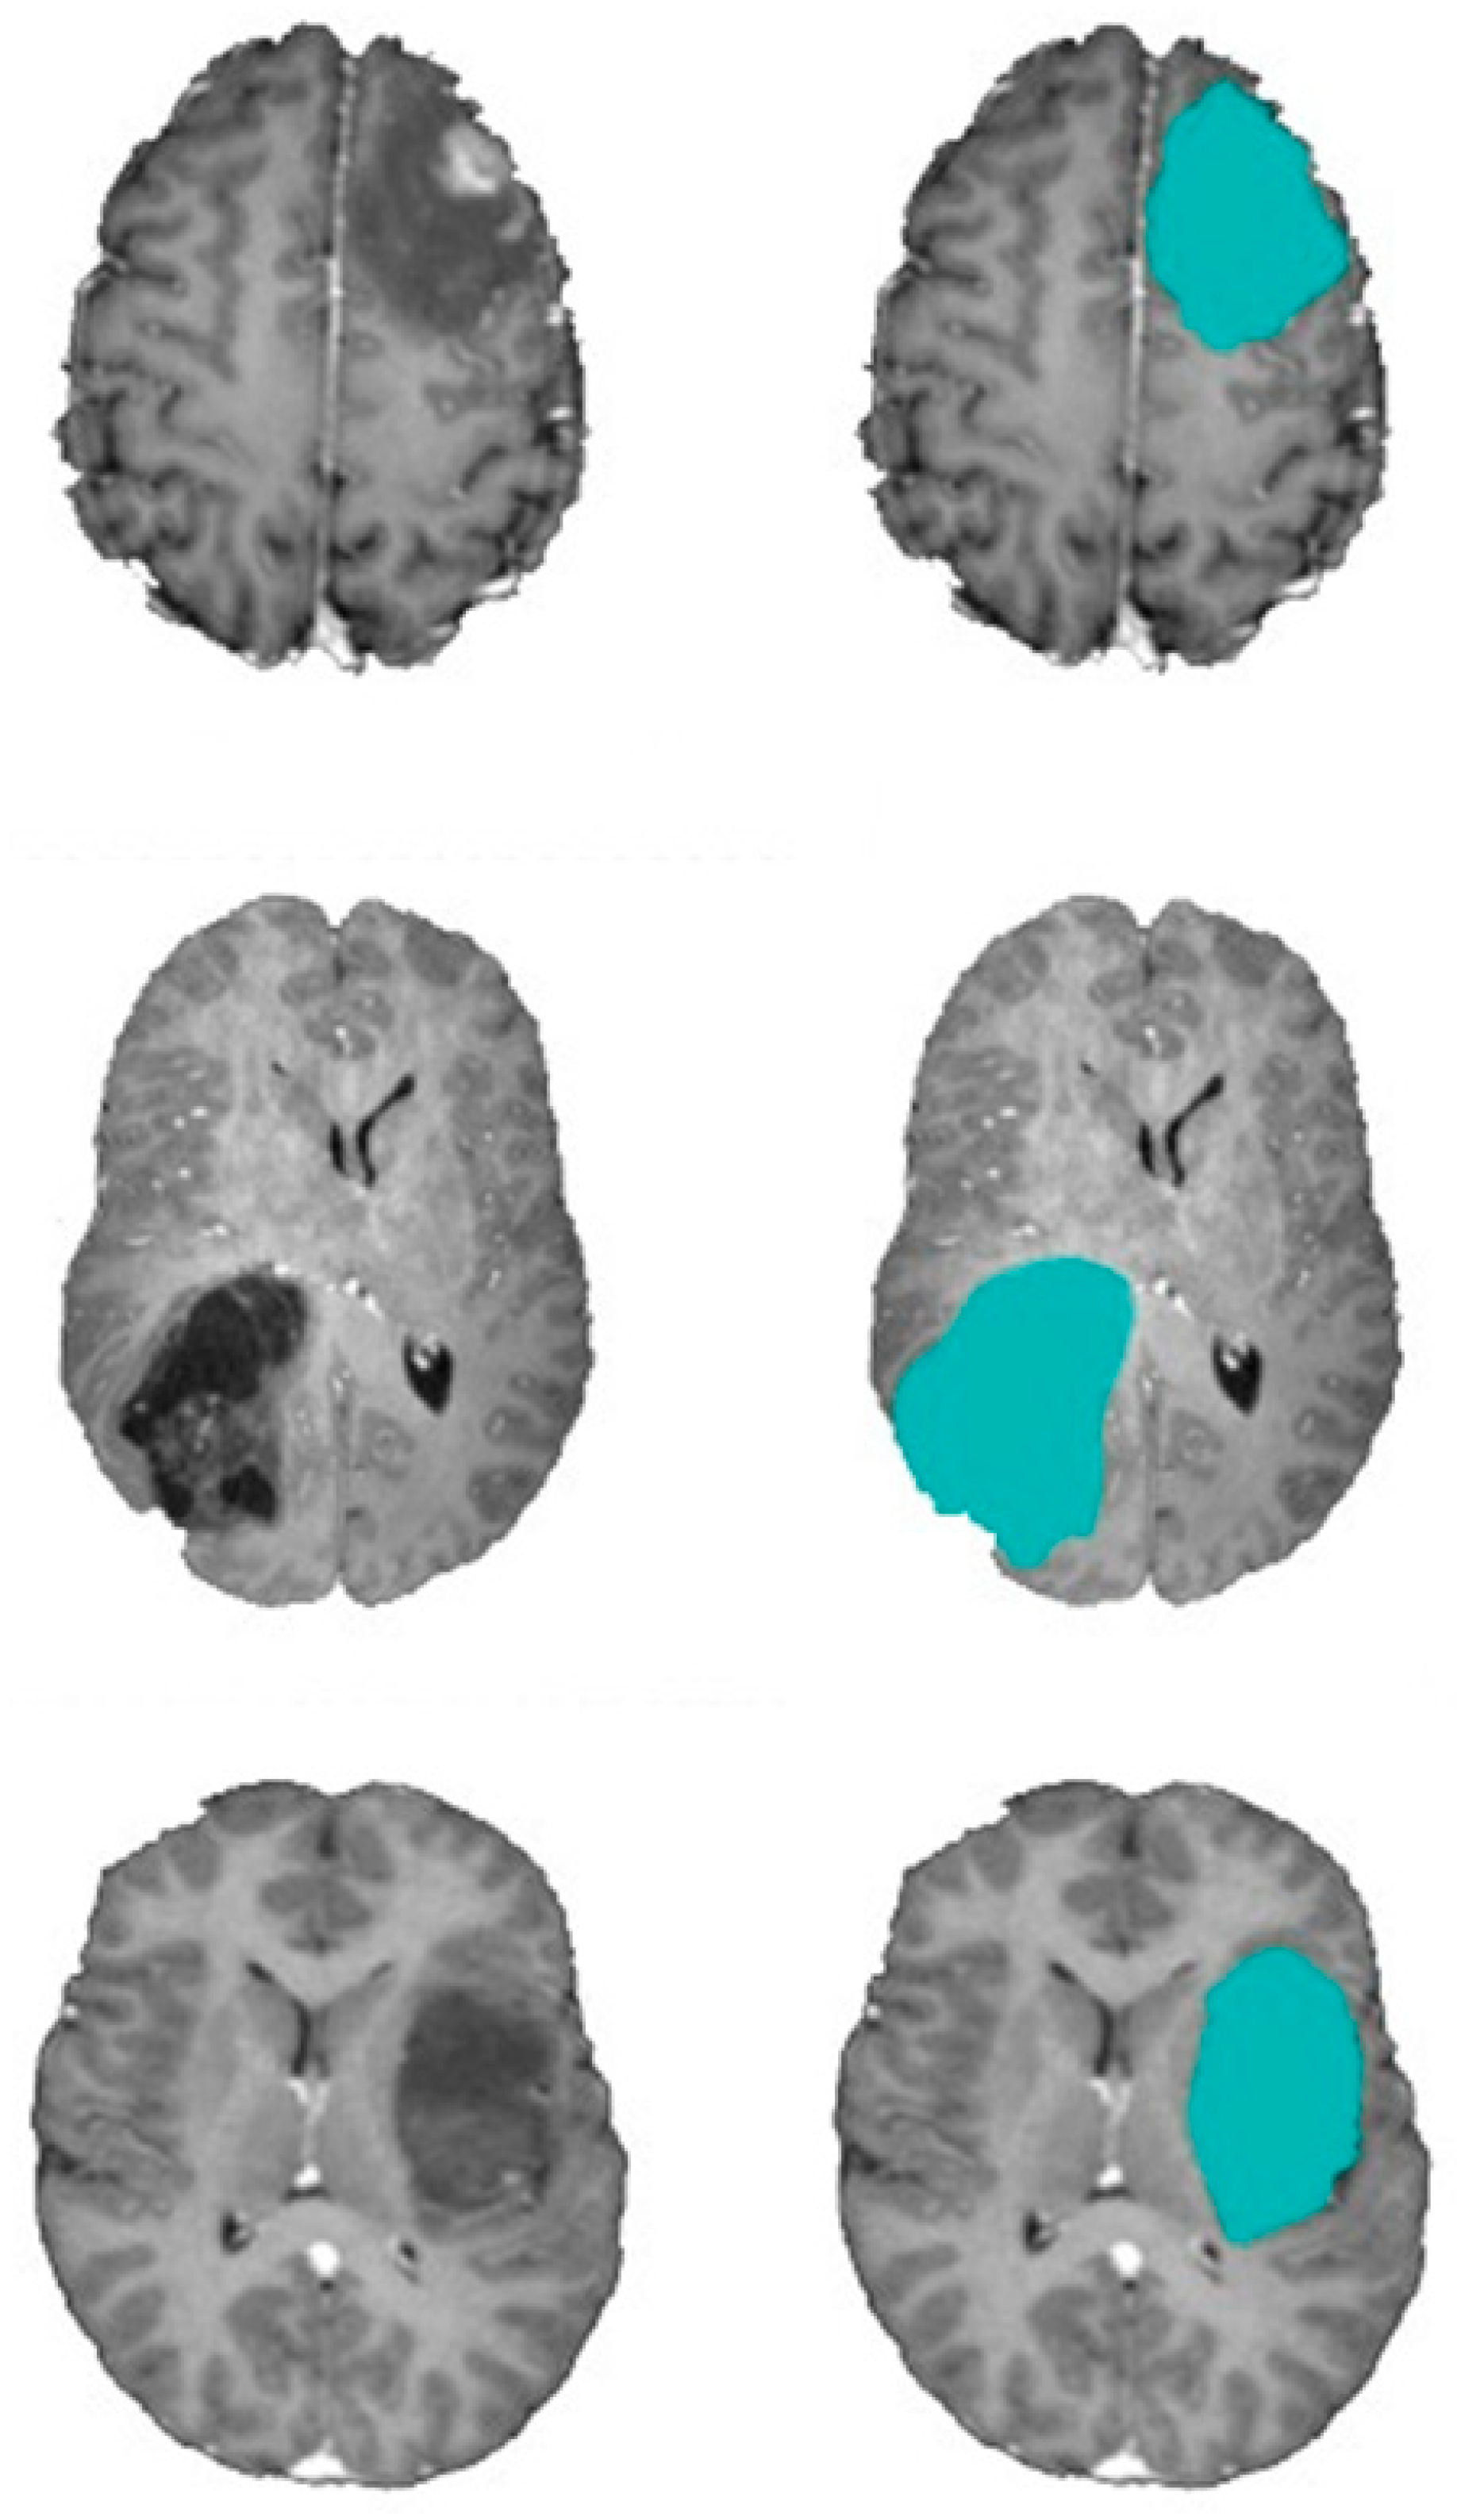

- Khalil, H.; Darwish, S.; Ibrahim, Y.; Hassan, O. 3D-MRI brain tumor detection model using modified version of level set segmentation based on dragonfly algorithm. Symmetry 2020, 12, 1256. [Google Scholar] [CrossRef]